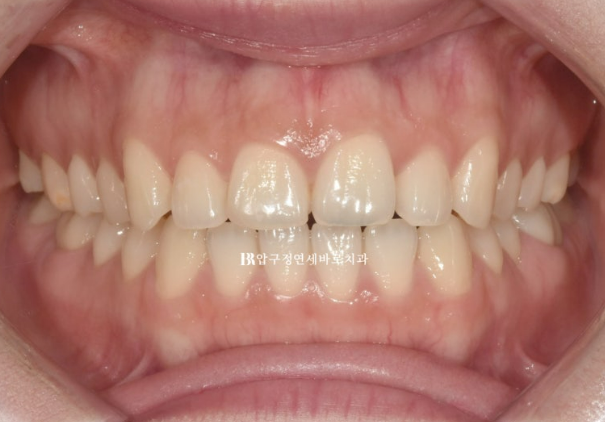

This patient visited for no-prep laminate treatment.

They had already completed orthodontic treatment a long time ago.

The retainer attached after orthodontic treatment came off, and the front teeth have become spaced apart.

Let’s look at the patient’s smile line.

The line connecting the teeth is straight.

This is called a reverse flat smile.

It feels awkward when smiling.